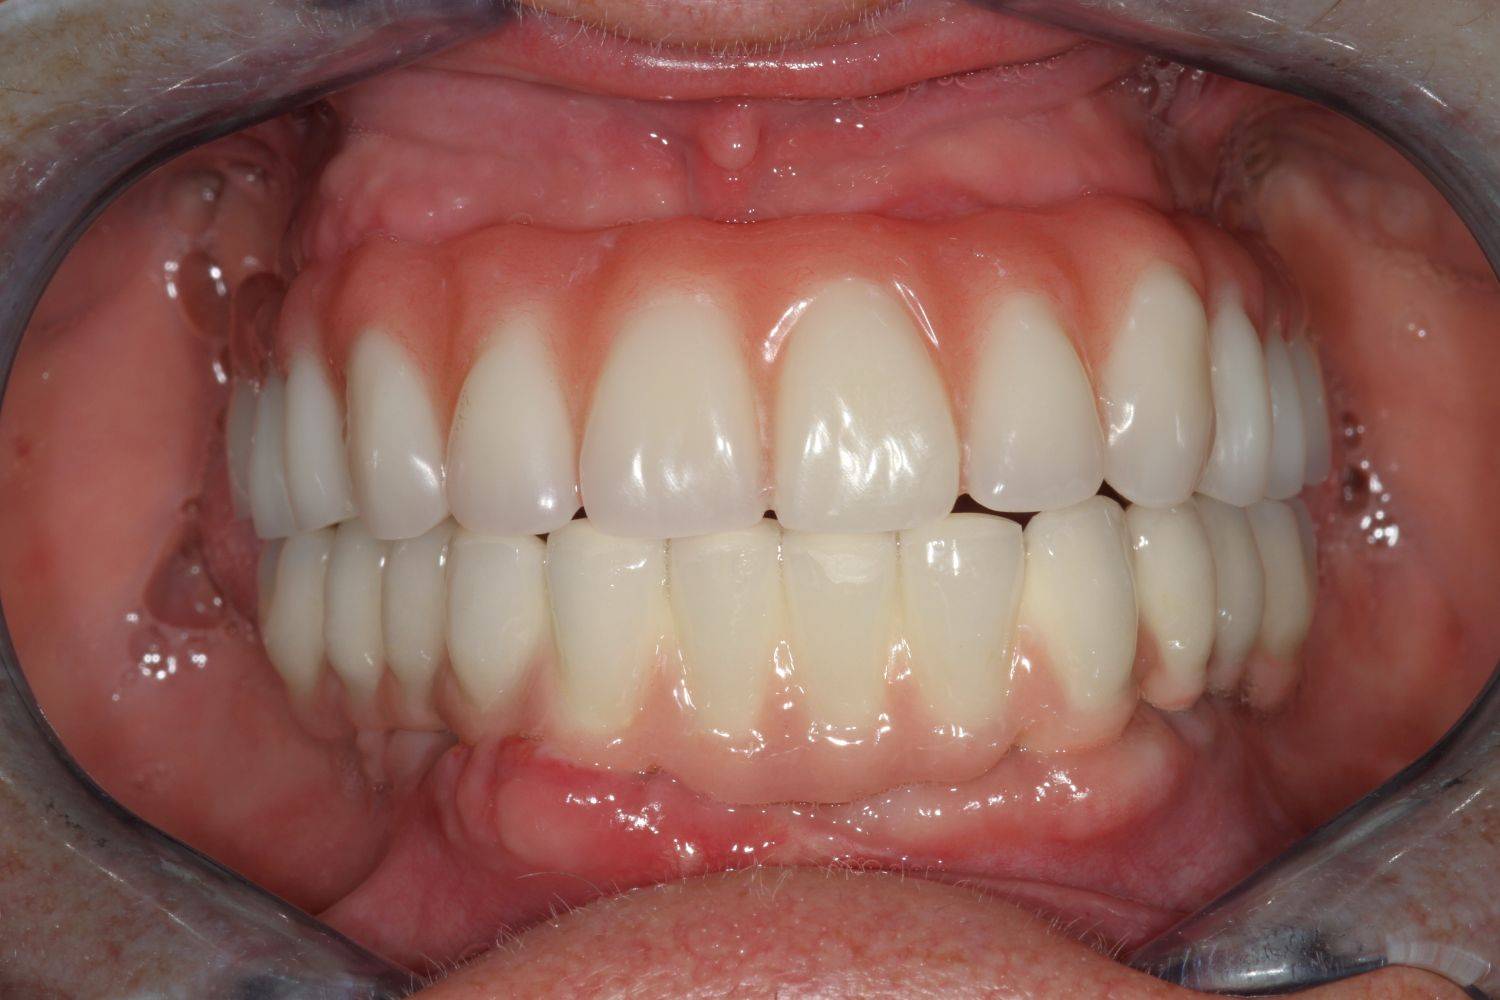

6. Eset

Nagymértékű fogkopás, erózió, csikorgatás a teljes rágóapparátust túlterhelve okoz reménytelennek tűnő helyzeteket.

Ebben az esetben implantátumok , koronák és hidak segítségével változtattunk a páciens fogainak érintkezésén. 6 hónapig ideiglenes hidakkal teszteltük a megváltoztatott harapási pozíciót. Ezután készültek el a végleges fix pótlások.